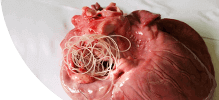

ГЕЛЬМИНТЫ ПОРАЖАЮТ ИЗНУТРИ, РАЗМНОЖАЮТСЯ И ВЫЗЫВАЮТ СМЕРТЕЛЬНЫЕ ЗАБОЛЕВАНИЯ!

Самки паразитов откладывают до 240 000 яиц в кишечнике человека ежедневно.

Размеры гельминтов (глистов) колеблются от нескольких сантиметров до 7-10 метров.